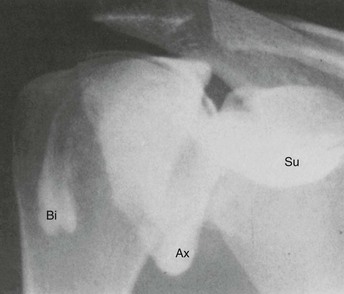

In the past, conventional arthrography of the shoulder (Fig. 44-2) was considered the gold standard for diagnosis of tears of the rotator cuff.5 Partial-thickness articular-sided rotator cuff tears, as well as adhesive capsulitis, are also accurately depicted with use of this method. However, partial-thickness rotator cuff tears involving the bursal surface and intrasubstance tears are not demonstrated by conventional shoulder arthrography, and its usefulness in the evaluation of glenohumeral instability is limited. This procedure is no longer widely performed.

Although many variations in technique exist, a method for performing arthrography prior to MRI or CT typically begins with a review of prior radiographs or the appropriate scout films of the affected shoulder. This review ensures identification of abnormalities such as soft tissue calcifications, postsurgical changes, and possible evidence of trauma or instability. Standard scout films include AP projections of the shoulder in internal and external rotation and an axillary lateral projection. The patient is then placed supine on the fluoroscopic table with the arm positioned next to the body in slight external rotation. The anterior skin is prepared and draped in a sterile manner, and the site of joint puncture is determined fluoroscopically. A point is chosen overlying the lower third of the humeral head about 0.5 cm lateral to the medial cortex of the humeral head. An alternative anterior approach is through the rotator interval10 or a posterior approach.11 The experience of the arthrographer often dictates the approach. Knowledge of all three approaches allows for tailored techniques based on the clinical situation. Although not directly proven in the literature, a posterior approach may permit more consistent visualization of the anterior capsule structures. The skin is anesthetized with 1% lidocaine (Xylocaine) with a 25-gauge, 0.75-inch needle or ethyl chloride spray. A 22-gauge, 3.5-inch or 1.5-inch spinal needle is then used to enter the joint. The correct position is verified fluoroscopically by injecting a small amount of radiopaque contrast material. If the needle is correctly positioned within the joint, the contrast material will outline the medial surface of the humeral head and spill into the subscapularis recess and axillary pouch (Fig. 44-3).

A total injection volume of 12 to 14 mL of material provides adequate distention of the shoulder joint without undue discomfort. Injection of a larger volume often leads to decompression of the joint through a weak point of the capsular insertion along the medial aspect of the subscapularis recess, resulting in leakage of contrast material into the adjacent soft tissues. This phenomenon degrades the quality of the examination and should be avoided. The diagnosis of adhesive capsulitis is made by identifying increasing resistance to the contrast material with a small injected volume, as well as by noting an abnormally small axillary pouch and a small or absent subscapularis recess. If increased pressure is encountered during injection of the contrast agent, fluoroscopic observation should be performed to ensure that the needle tip remains intraarticular. If the contrast agent is intraarticular, the diagnosis of adhesive capsulitis is made, injection of contrast material is ceased, and the needle is withdrawn. Most practices use an iodinated contrast agent for CTA and a dilute gadolinium solution for MRA. The contrast agent can be mixed with 0.1 to 0.3 mL of 1 : 1000 epinephrine to prolong retention of the contrast agent within the joint, thus allowing adequate time for transportation of the patient to the CT or MRI scanner and for imaging. Imaging should be performed as soon as possible after injection of the contrast agent to minimize resorption of contrast material.